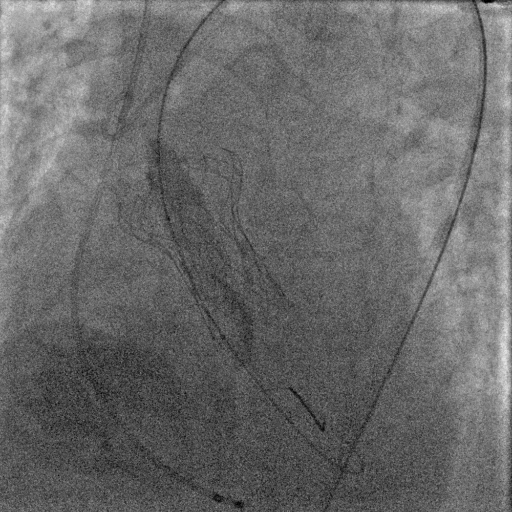

释放完成后基本无压差,但是造影和经胸超声显示少量反流,并且位于左窦,基本可以判断和钙化相关,所以陶凌主任在和线上专家讨论后决定选用22mm的球囊进行后扩。

17.gif

球囊后扩

后扩完成后瓣膜形态明显改善,造影显示基本无反流。整台手术圆满完成。